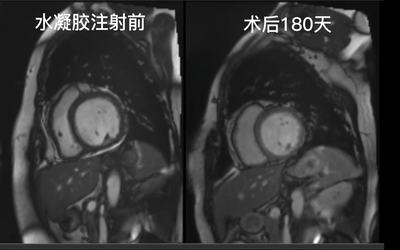

國內(nèi)創(chuàng)新公司德柯醫(yī)療研發(fā)出的新型心衰治療技術(shù)——經(jīng)導(dǎo)管心內(nèi)膜水凝膠植入術(shù),近期已由空軍軍醫(yī)大學(xué)西京醫(yī)院完成10例FIM研究。由完成6個(gè)月隨訪的患者術(shù)前術(shù)后MRI影像觀察可得,患者左心室形態(tài)有較為明顯的改善。

患者術(shù)前與術(shù)后180天時(shí)MRI影像對(duì)比

患者男,55歲。心臟磁共振影像顯示左心室擴(kuò)大,MRI顯示該患者LVEF、LVEDVI 和LVESVI分別為16%、234ml/m2 和 196.8ml/m2;

診斷為擴(kuò)張型心肌病,接受最佳藥物治療后仍出現(xiàn)失代償性心力衰竭,NYHA心功能Ⅳ級(jí);

在 6 個(gè)月的隨訪中,患者的臨床狀況顯著改善(NYHA心功能 II 級(jí))。MRI顯示LVEF 為 22%,LVEDVI (188.25 mL/m2)和LVESVI (146.36 mL/m2)降低。